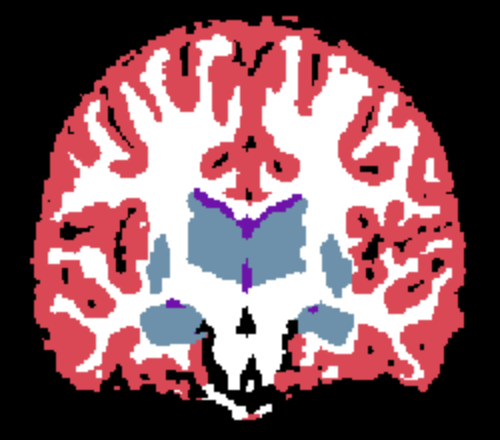

Here, we use both the INU model described in Equation 7 and the homogeneous noise model described in Equation 8. For the former, we use random fields with increasing spatial frequency (). We denote the corresponding learnable parameters , and , with preset values . Noise-free target “real”, and learned images are shown in Figure 2. Inference results for the value of the noise parameter are reported in Table 3, and are in line with those obtained in the noise-only experiment.

| (a) Noise-free image | (b) Learned image | (c) Real image |